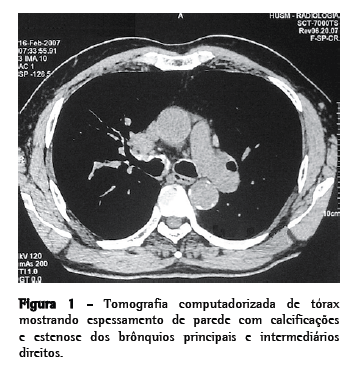

Homem de 67 anos, aposentado, hipertenso, ex-fumante e ex-etilista, foi encaminhado ao nosso serviço com queixas de dispnéia progressiva, sibilância e dor torácica nos últimos 6 meses. Uma radiografia de tórax obtida 8 anos antes mostrava aumento hilar direito. Tinha também uma história de longa duração de episódios de hemoptise que cessaram 10 anos antes, assim como uma história de infecções respiratórias recorrentes. No exame físico, apresentava murmúrio vesicular diminuído e crepitações leves nas bases pulmonares. Uma segunda radiografia de tórax apresentou as mesmas características da primeira. Os resultados dos testes de função pulmonar (espirometria e teste de caminhada de seis minutos) e dos testes laboratoriais estavam dentro dos limites da normalidade. Uma recente tomografia computadorizada de tórax mostrava estenose parcial dos brônquios principais e intermediários direitos e calcificações mucosas laminares que se estendiam do terço superior da traquéia para áreas estenóticas inferiores, assim como linfoadenomegalias mediastinais (Figura 1). Uma amostra de escarro induzido foi negativa para bactérias, bacilos álcool-ácido resistentes e fungos. O lavado broncoalveolar revelou um processo inflamatório inespecífico.

A amiloidose traqueobrônquica é uma doença rara resultante da deposição anormal de proteínas sob a mucosa da traquéia e dos grandes ­brônquios­.­(1-7) É uma doença de progressão lenta que exige evidências histopatológicas para a confirmação do diagnóstico.(2,4,5) A amiloidose traqueobrônquica ocorre tipicamente em pacientes entre 40 e 50 anos, constituindo 0,5% das lesões traqueobrônquicas sintomáticas.(2,4) São sintomas comuns a tosse crônica, dispnéia, sibilância, hemoptise e pneumonias recorrentes.(2-12) Foram reportados casos de amiloidose traqueobrônquica que simulam asma de difícil manejo.(12) Metade de todos os pacientes apresenta radiografia de tórax normal; as alterações mais comuns são atelectasia lobar, calcificações brônquicas, bronquiectasias e adenopatia hilar.(4,11) A tomografia computadorizada de tórax e a fibrobroncoscopia revelam espessamento de parede brônquica, estreitamento irregular do lúmen das vias aéreas e nódulos calcificados dentre a ­submucosa­.­(3,4,6). A tomografia computadorizada pode sugerir o diagnóstico, mas a fibrobroncoscopia permite uma visualização melhor das lesões e tem a vantagem de permitir a obtenção de amostras para a análise histopatológica. Na maioria dos casos, o diagnóstico é atingido somente após exames seqüenciais de fibrobroncoscopia.